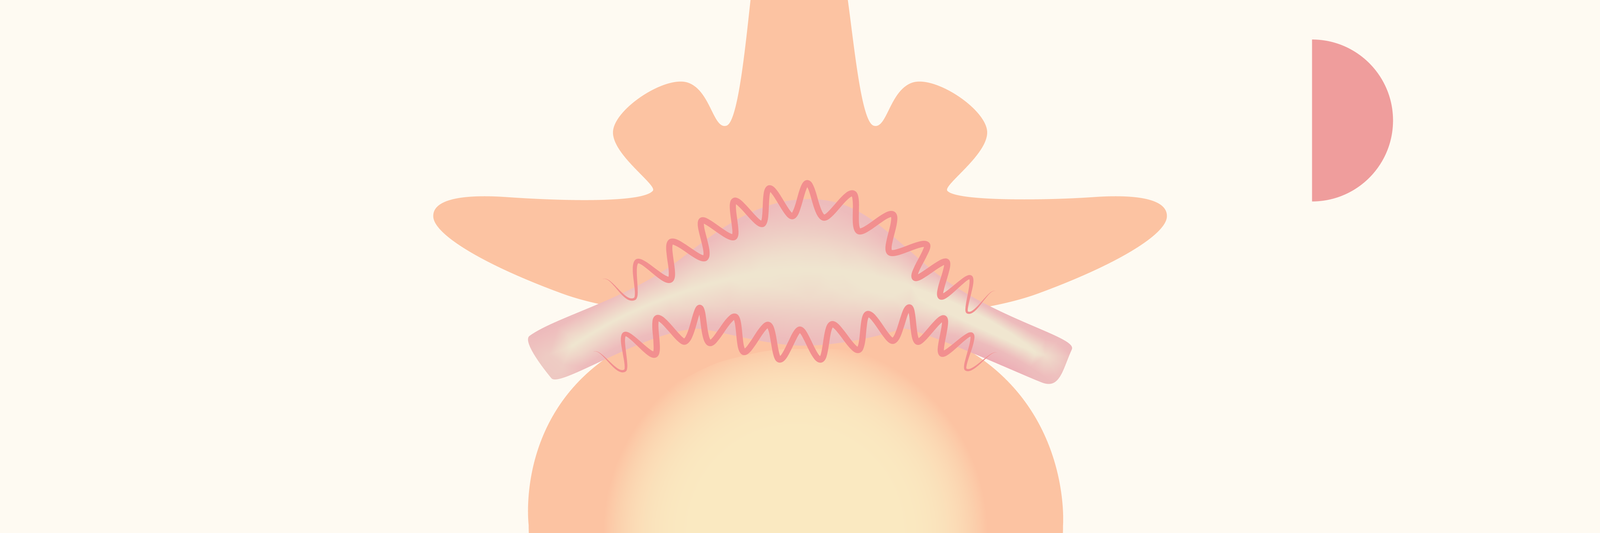

U heeft mogelijk al de diagnose gekregen, of u zoekt juist meer duidelijkheid over een hernia of wervelkanaalvernauwing (stenose) in uw rug of nek. Hieronder vindt u uitgebreide informatie vanuit meerdere perspectieven. Ook leest u wat een kijkoperatie in uw situatie kan betekenen.